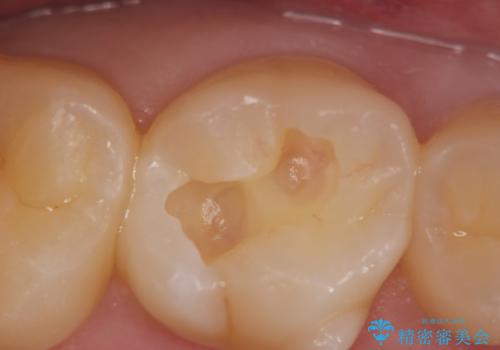

- 検診を希望され来院されました。

症状は特にありませんでしたが、検診で全体をチェックすることで虫歯を小さなうちに早期発見し治療することができました。

虫歯は放置すると大きくなり、神経まで達し根管治療が必要になったり抜歯に至ることもある進行性の病気です。

早期の発見・治療をすることで期間も費用も少なくすることができます。